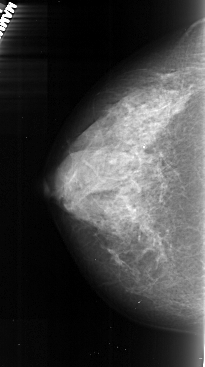

A_1037_1.LEFT_CC

LEFT_CC LINES 4771 PIXELS_PER_LINE 2656 BITS_PER_PIXEL 16 RESOLUTION 42 NON_OVERLAY